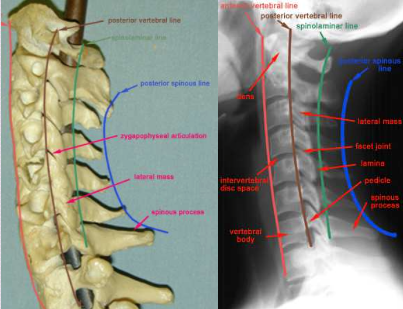

Red : Anterior vertebral line

Brown : Posterior vertebral line

Green : Spinal laminar line

Blue : Posterior spinous process line